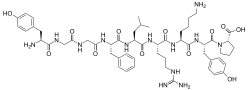

Opioid peptides

Enkephalins

Structures

| Enkephalins | ||||

|---|---|---|---|---|

DAMGO DAMGO |

||||